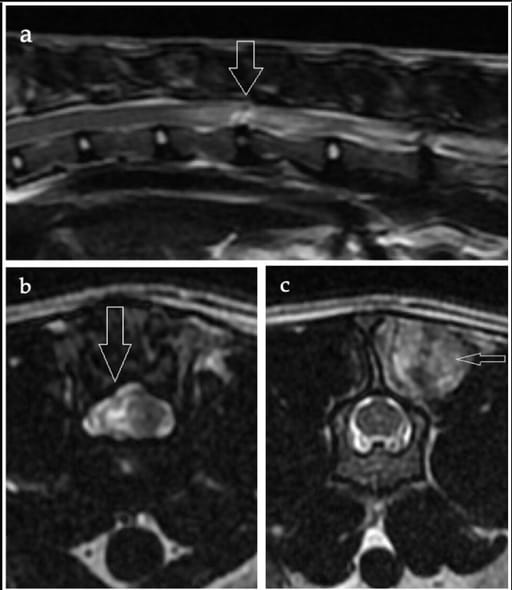

(a) Sagittal T2-weighted image of the thoracolumbar vertebral column, (b) transverse T2-weighted image at the level of the T13–L1 intervertebral disc space, and (c) transverse T2-weighted image at the level of the L2 vertebral body of a domestic shorthair cat aged 3 years 5 months. (a) A linear hypointense tract extends from the T13–L1 intervertebral disc into the spinal cord parenchyma, surrounded by an ill-defined hyperintense area (arrow). The T13–L1 nucleus pulposus shows a reduced volume compared with the adjacent discs. (b) Right-sided intramedullary changes are evident at the level of the T13–L1 intervertebral disc (arrow), with no apparent extraneous material in the epidural space. (c) A relatively well-demarcated hyperintensity within the epaxial musculature at the level of the L2 vertebral body, suggestive of epaxial muscle contusion or oedema (not haemorrhage, based on excluded T2*-weighted gradient-recall echo images), was considered potentially indicative of external trauma or secondary to the extrusion (arrow)